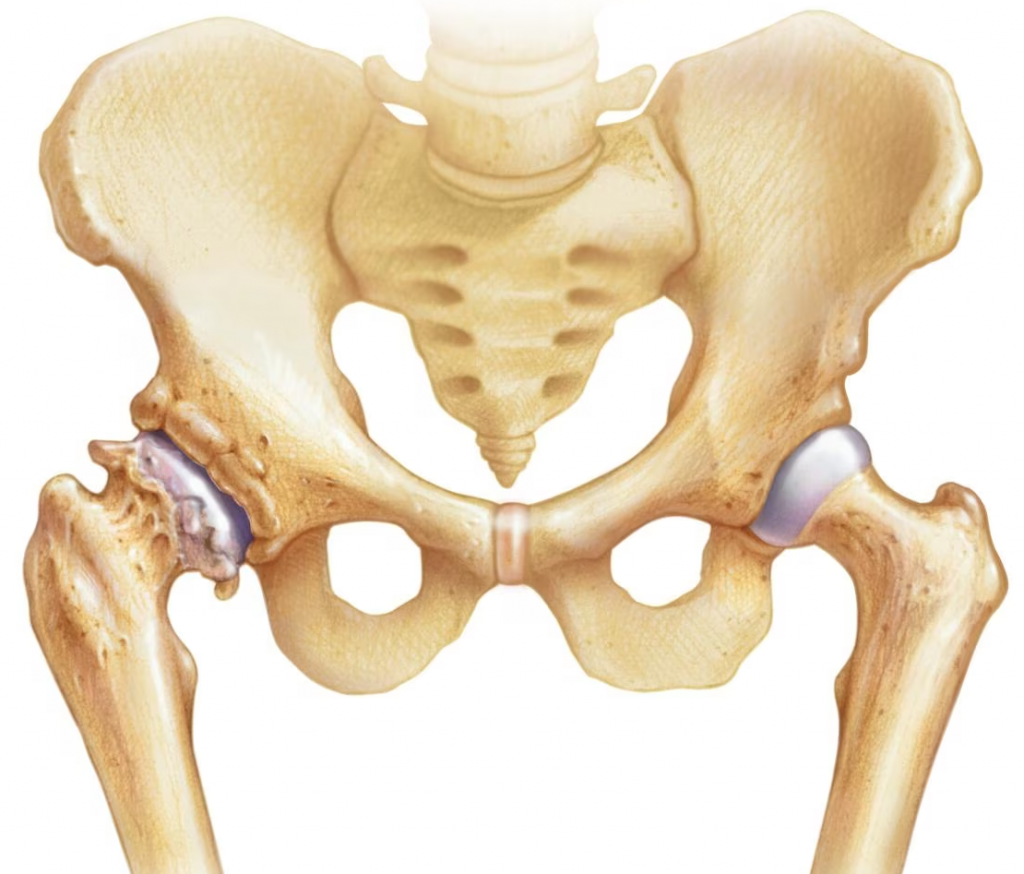

La hanche fonctionne comme une balle dans une cavité. La balle, c’est la tête du fémur, et la cavité, c’est l’acetabulum ou cotyle, qui appartient à l’os du bassin. Les deux os sont recouvertes d’un cartilage, un revêtement très lisse, qui permet à la hanche de bouger et marcher sans frottement. L’arthrose, c’est quand ce cartilage s’use, se raye ou se fissure. Si la surface n’est plus lisse, les mouvements de la hanche « accrochent » et on peut avoir mal en marchant, et une raideur.

- Des malformations de la hanche : La dysplasie et la luxation congénitale de hanche par exemple peuvent favoriser le développement d’une arthrose précoce.

- L’ostéonécrose de la tête fémorale : Cette pathologie affecte des personnes souvent jeunes, à cause de différents facteurs favorisants (drépanocytose, alcool, traitement prolongé par cortisone…). La tête du fémur s’abîme sur plusieurs mois, et évolue vers une arthrose quand le cartilage est touché à son tour.